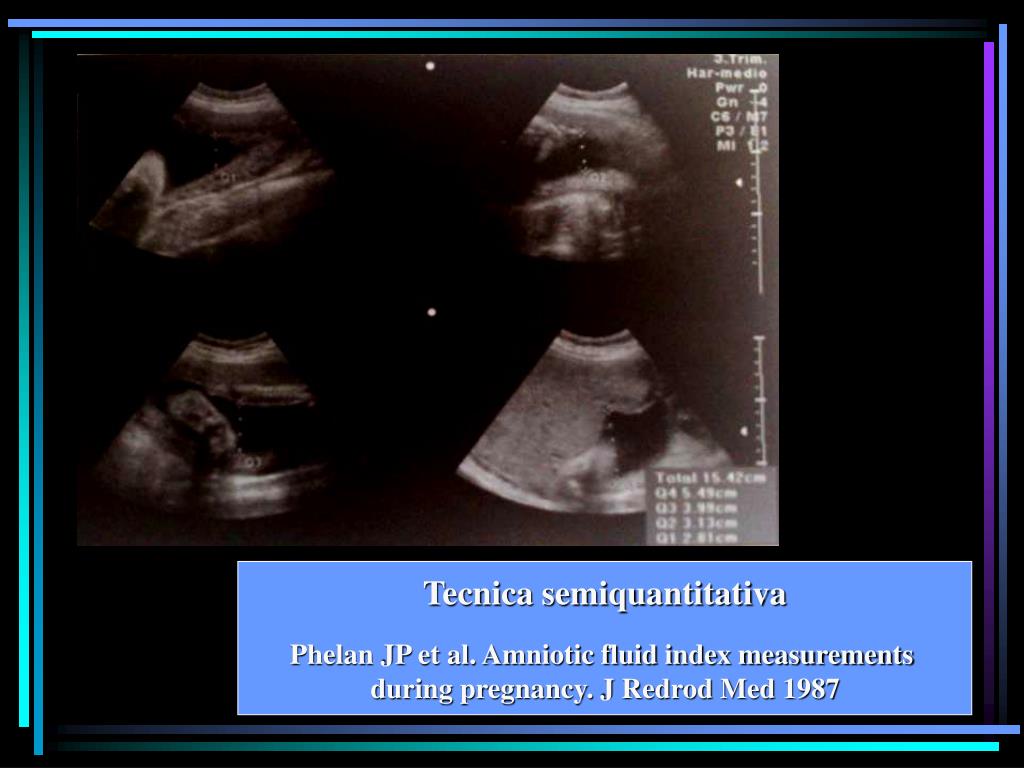

28. Tecnica semiquantitativa Phelan JP et al. Amniotic fluid index measurements during pregnancy. J Redrod Med 1987